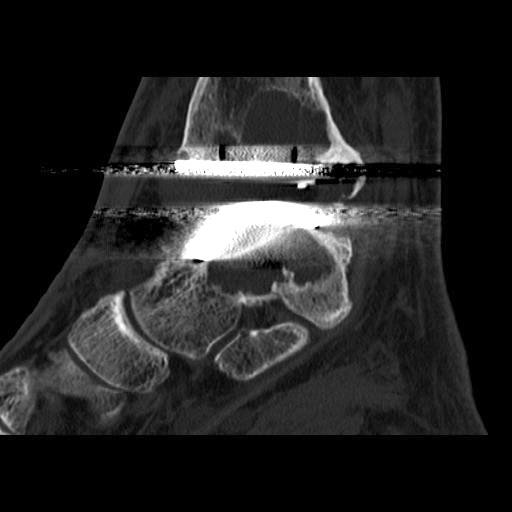

2. Periartikuläre Zystenbildung (Abb. 23) 15.